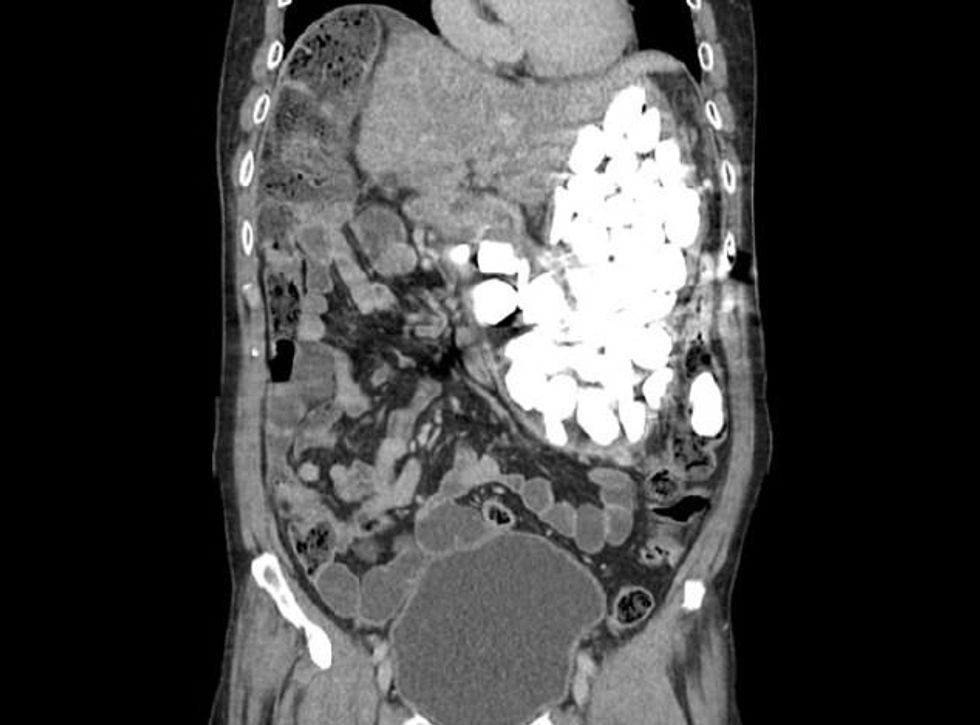

Gurë, kapakë të shisheve dhe disa objekte tjera, janë gjetur në barkun e 54-vjeçarit, pasi i kishte përpirë për një kohë të gjatë, në përpjekje që ta ndalonte ankthin dhe depresionin, transmeton Telegrafi.

Trupi tij e ka pasur të pamundur t’i tretë këto objekte të forta, duke i shkaktuar dhimbje të mëdha dhe mungesë energjie, sepse ishte gjithnjë i fryrë dhe nuk mund të ushqehej si duhej.

Fillimisht, u provua që gurët t’i largohen me gastroskopi, por sasia ishte aq e madhe, sa që u pamundësua përdorja e kësaj teknike.

Intervenimi kirurgjik ka përfunduar me sukses, ndërsa rasti i rrallë po shqyrtohet nga ekspertët e mjekësisë, për shkak të sasisë enorme të objekteve të grumbulluara. /Telegrafi/